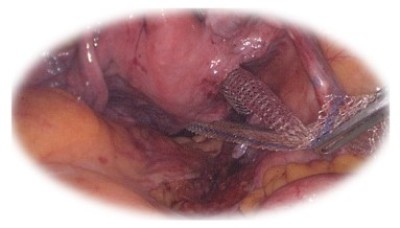

Promontofixația laparoscopică/ robotică:

• Tratament minim-invaziv al prolapsului genital

• Alternativă la chirurgia transvaginală, clasică

• Presupune implantarea unei proteze non- resorbabile pe cale abdominală pentru a corecta prolapsul genital

• Combină avantajele abordului transabdominal cu cele ale chirurgiei minim-invazive:

• Spațiu mare de lucru

• Identificare mai precisă a elementelor anatomice

• Sângerare minimă, recuperare rapidă

• Rată scăzută a recidivelor la 5 ani